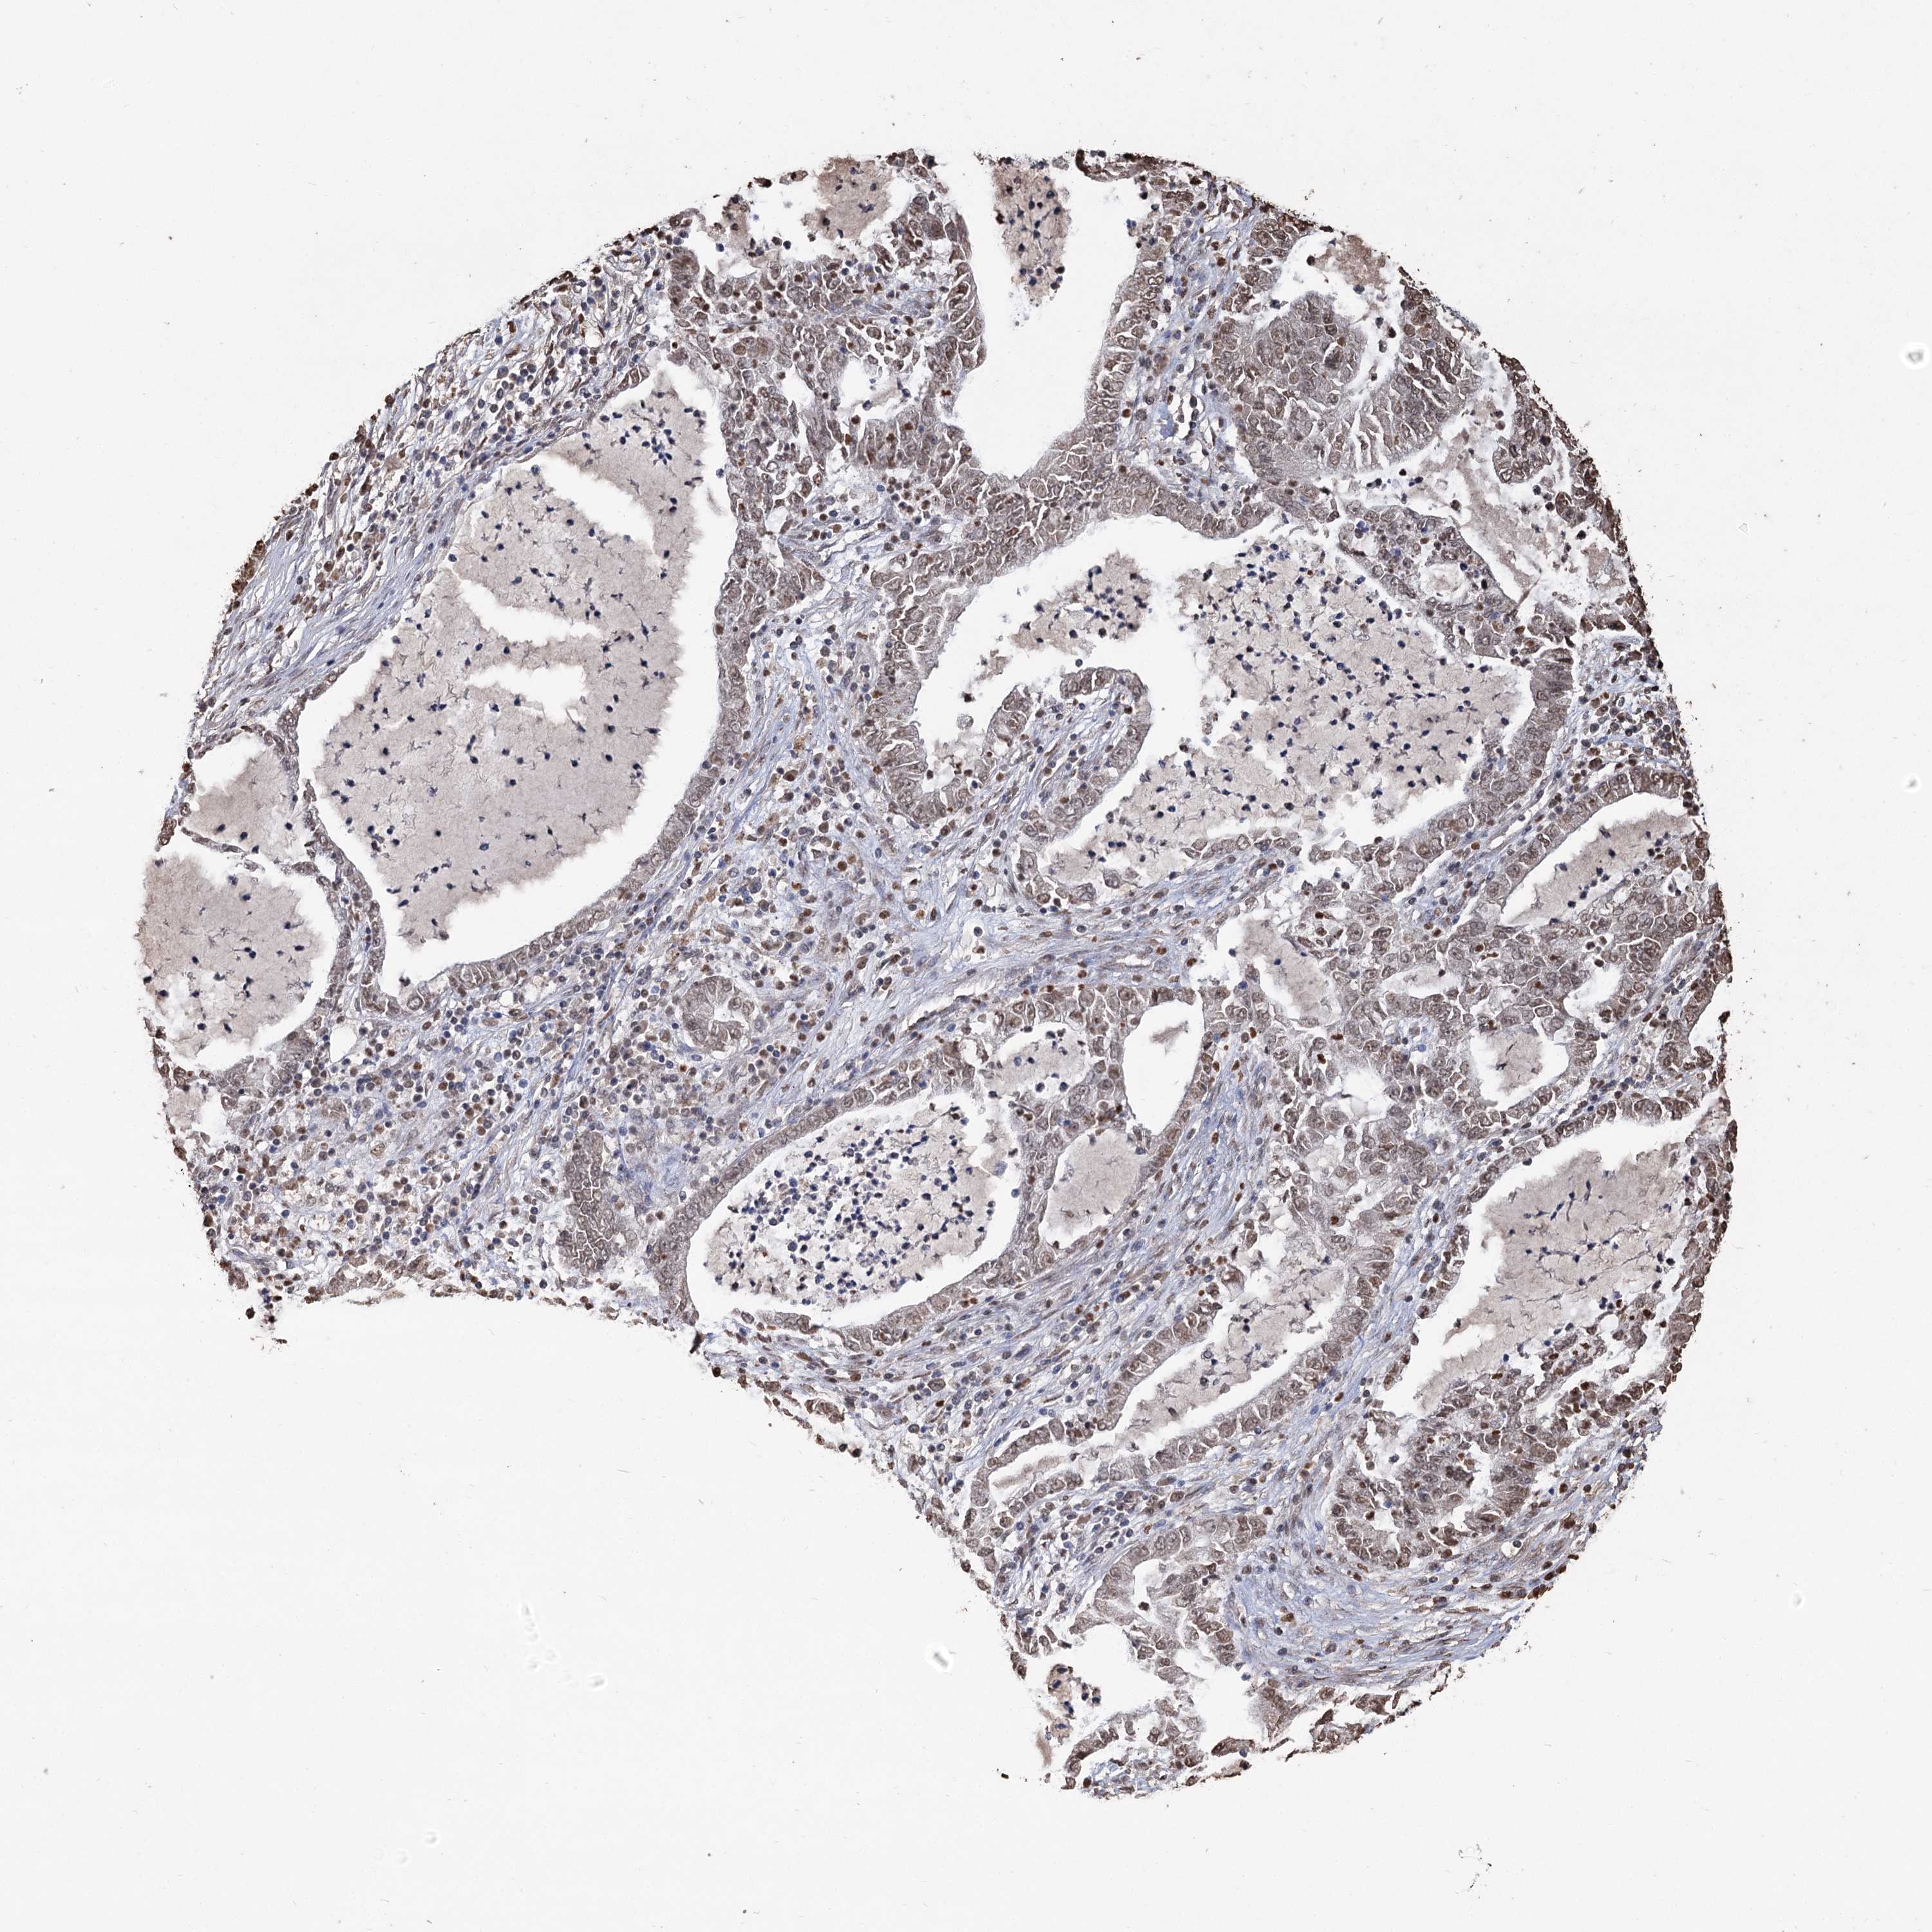

CANCER LUNG CANCER Show tissue menu

LUAD TCGA LUAD VALIDATION LUSC TCGA LUSC VALIDATION PROTEIN LUAD CPTAC PROTEIN LUSC CPTAC PROTEIN EXPRESSION

HBA1 is not prognostic in Lung Adenocarcinoma (TCGA)

Average pTPM 43.2

Number of samples 497